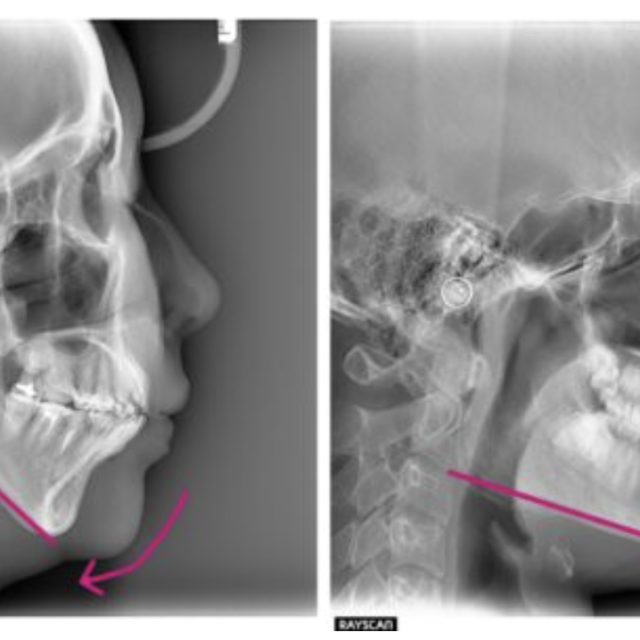

症例case05 Marfan症候群を伴う叢生症例 (14歳/女性 /6ヶ月)